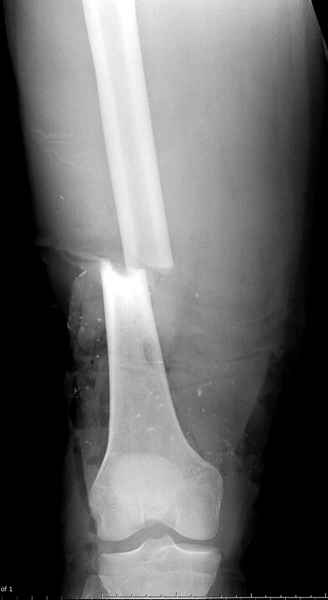

Тяжелый открытый внутрисуставной перелом дистальной части бедренной кости и открытый голени в средней трети,множественные раны и некрозы на голени. Что делать? 4 суток после мотоциклетной травмы. 16 лет. Переведен из районной больницы, где основные раны на голени и бедре были ушиты наглухо и наложено скелетное вытяжение за бугристость и пятку, через 2 суток. При поступлении - высокая лихорадка, анемия. Из сопутствующих только сотряс. Раны на бедре и голени расскрыты, обработаны. На передней поверхности бедра рана с начавшимся нагноением, около 15х8см, полость распространяется от места перелома, где значительная часть отломков практически лишена связи с мягкими тканями, до верхней трети, откуда удалена гематома 200мл. 4-главая мышца повреждена, отрыв и перелом без смещения надколенника. Проксимальный отломок бедренной кости на протяжении 20см на 2 трети окружности лишен надкостницы. Резко выраженный отек бедра. На голени рана на передней поверхности 12 х 5см, дном является лишенная надкостницы большеберцовая кость, некроз краев раны. Множественные раны и участки некрозов кожи в области коленного сустава, обширные некрозы на голени в нижней и верхней третях. Пульсация на стопе отчетливая, при этом некрозы в нижней трети голени постепенно увеличиваются. Сейчас на ИВЛ с клиникой респираторного дистресс синдрома. Что делать - неясно. Возможен ли при таком переломе бедра интрамедуллярный остеосинтез? Было бы здорово фиксировать оба перелома через 1 доступ.

Больному с политравмой установлен наружный "spanning-bridging" фиксатор, после нескольких Irrigation&Debridment на фоне отрицательного посева из раны, через открытый участок установлен 4.5 mm Locking Plate.

На фоне фиксированного перелома бедра мероприятия по восстановлению мягкотканого покрова. Перелом голени зафиксирован после стабилизации бедра традиционным методом.